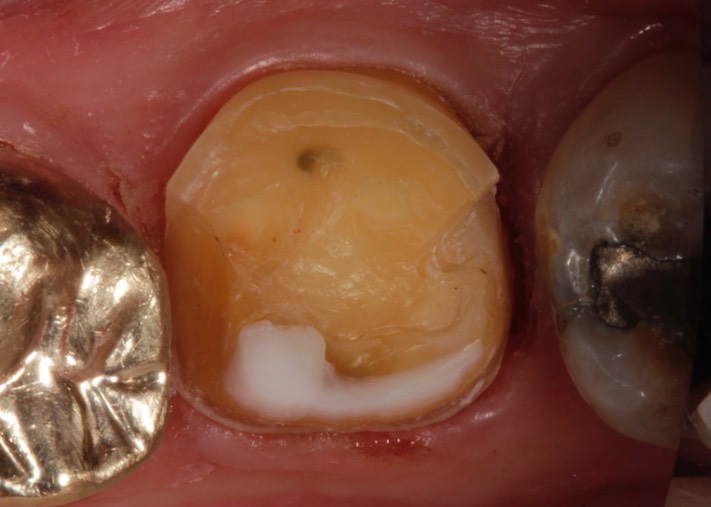

Larry Fujioka #18 prep